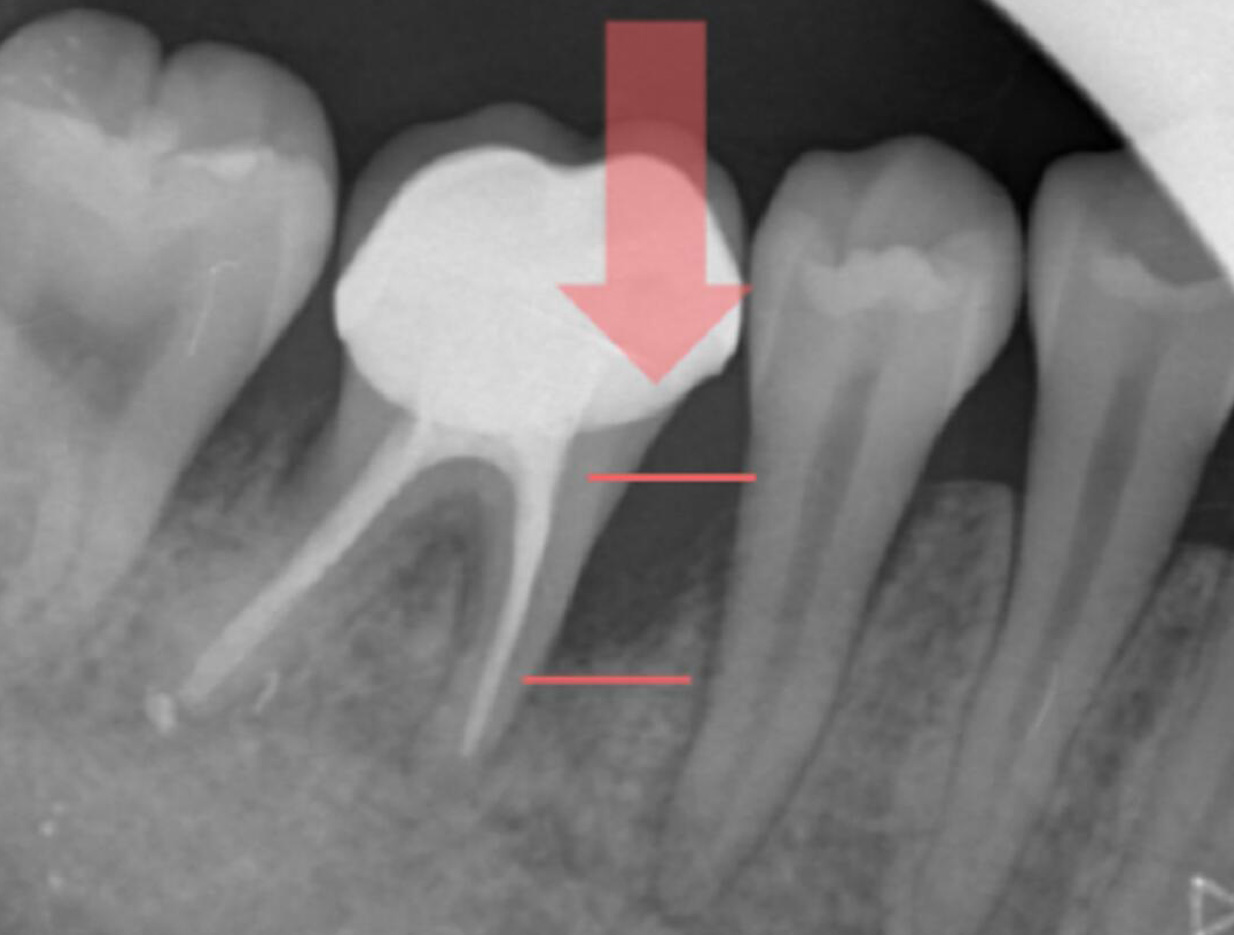

牙周再生手術前

X光片(紅色橫線之間黑色區域為骨頭喪失所在)